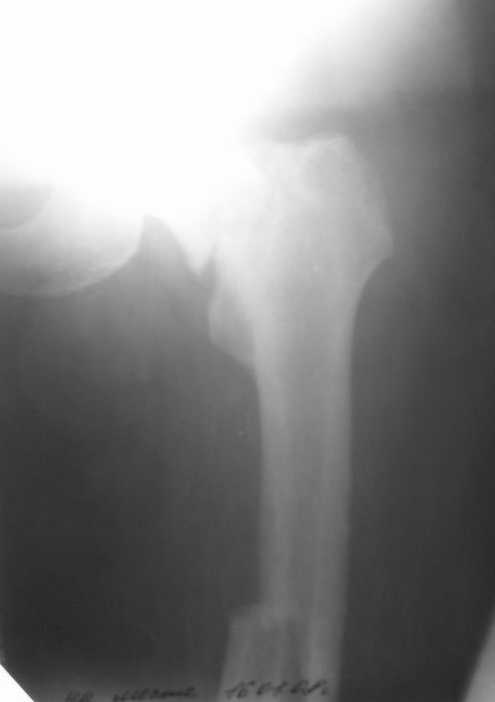

Лечился в ЦРБ. К нам поступил вчера. Имеется оскольчатый перелом диафиза левого бедра, перелом медиального мыщелка, краевой перелом надколенника. У нас, кроме того, выявили перелом шейки бедра. Перелом закрытый, имеется рана в в/3 голени(ниже уровня бугристости б/берцовой кости)без признаков инфицирования.Планируем закрыто фиксировать мыщелок и надколенник винтами, затем закрыто заштифтовать бедро. Вопрос возник по перелому шейки: что предпочесть - длинный PFN или DFN + DHS на шейку?Буду благодарен за ценные советы.С уважением, Станислав Дмитриев.

Заранее приношу извинения за качество снимков. То что есть - либо из ЦРБ, либо сделано в приемном покое, где дежурят рентгенлаборанты различной квалификации. Завтра постараемся сделать снимки всего бедра на длинные кассеты в 2 проекциях. Сейчас больной на скелетном вытяжении. Состояние стабильное.